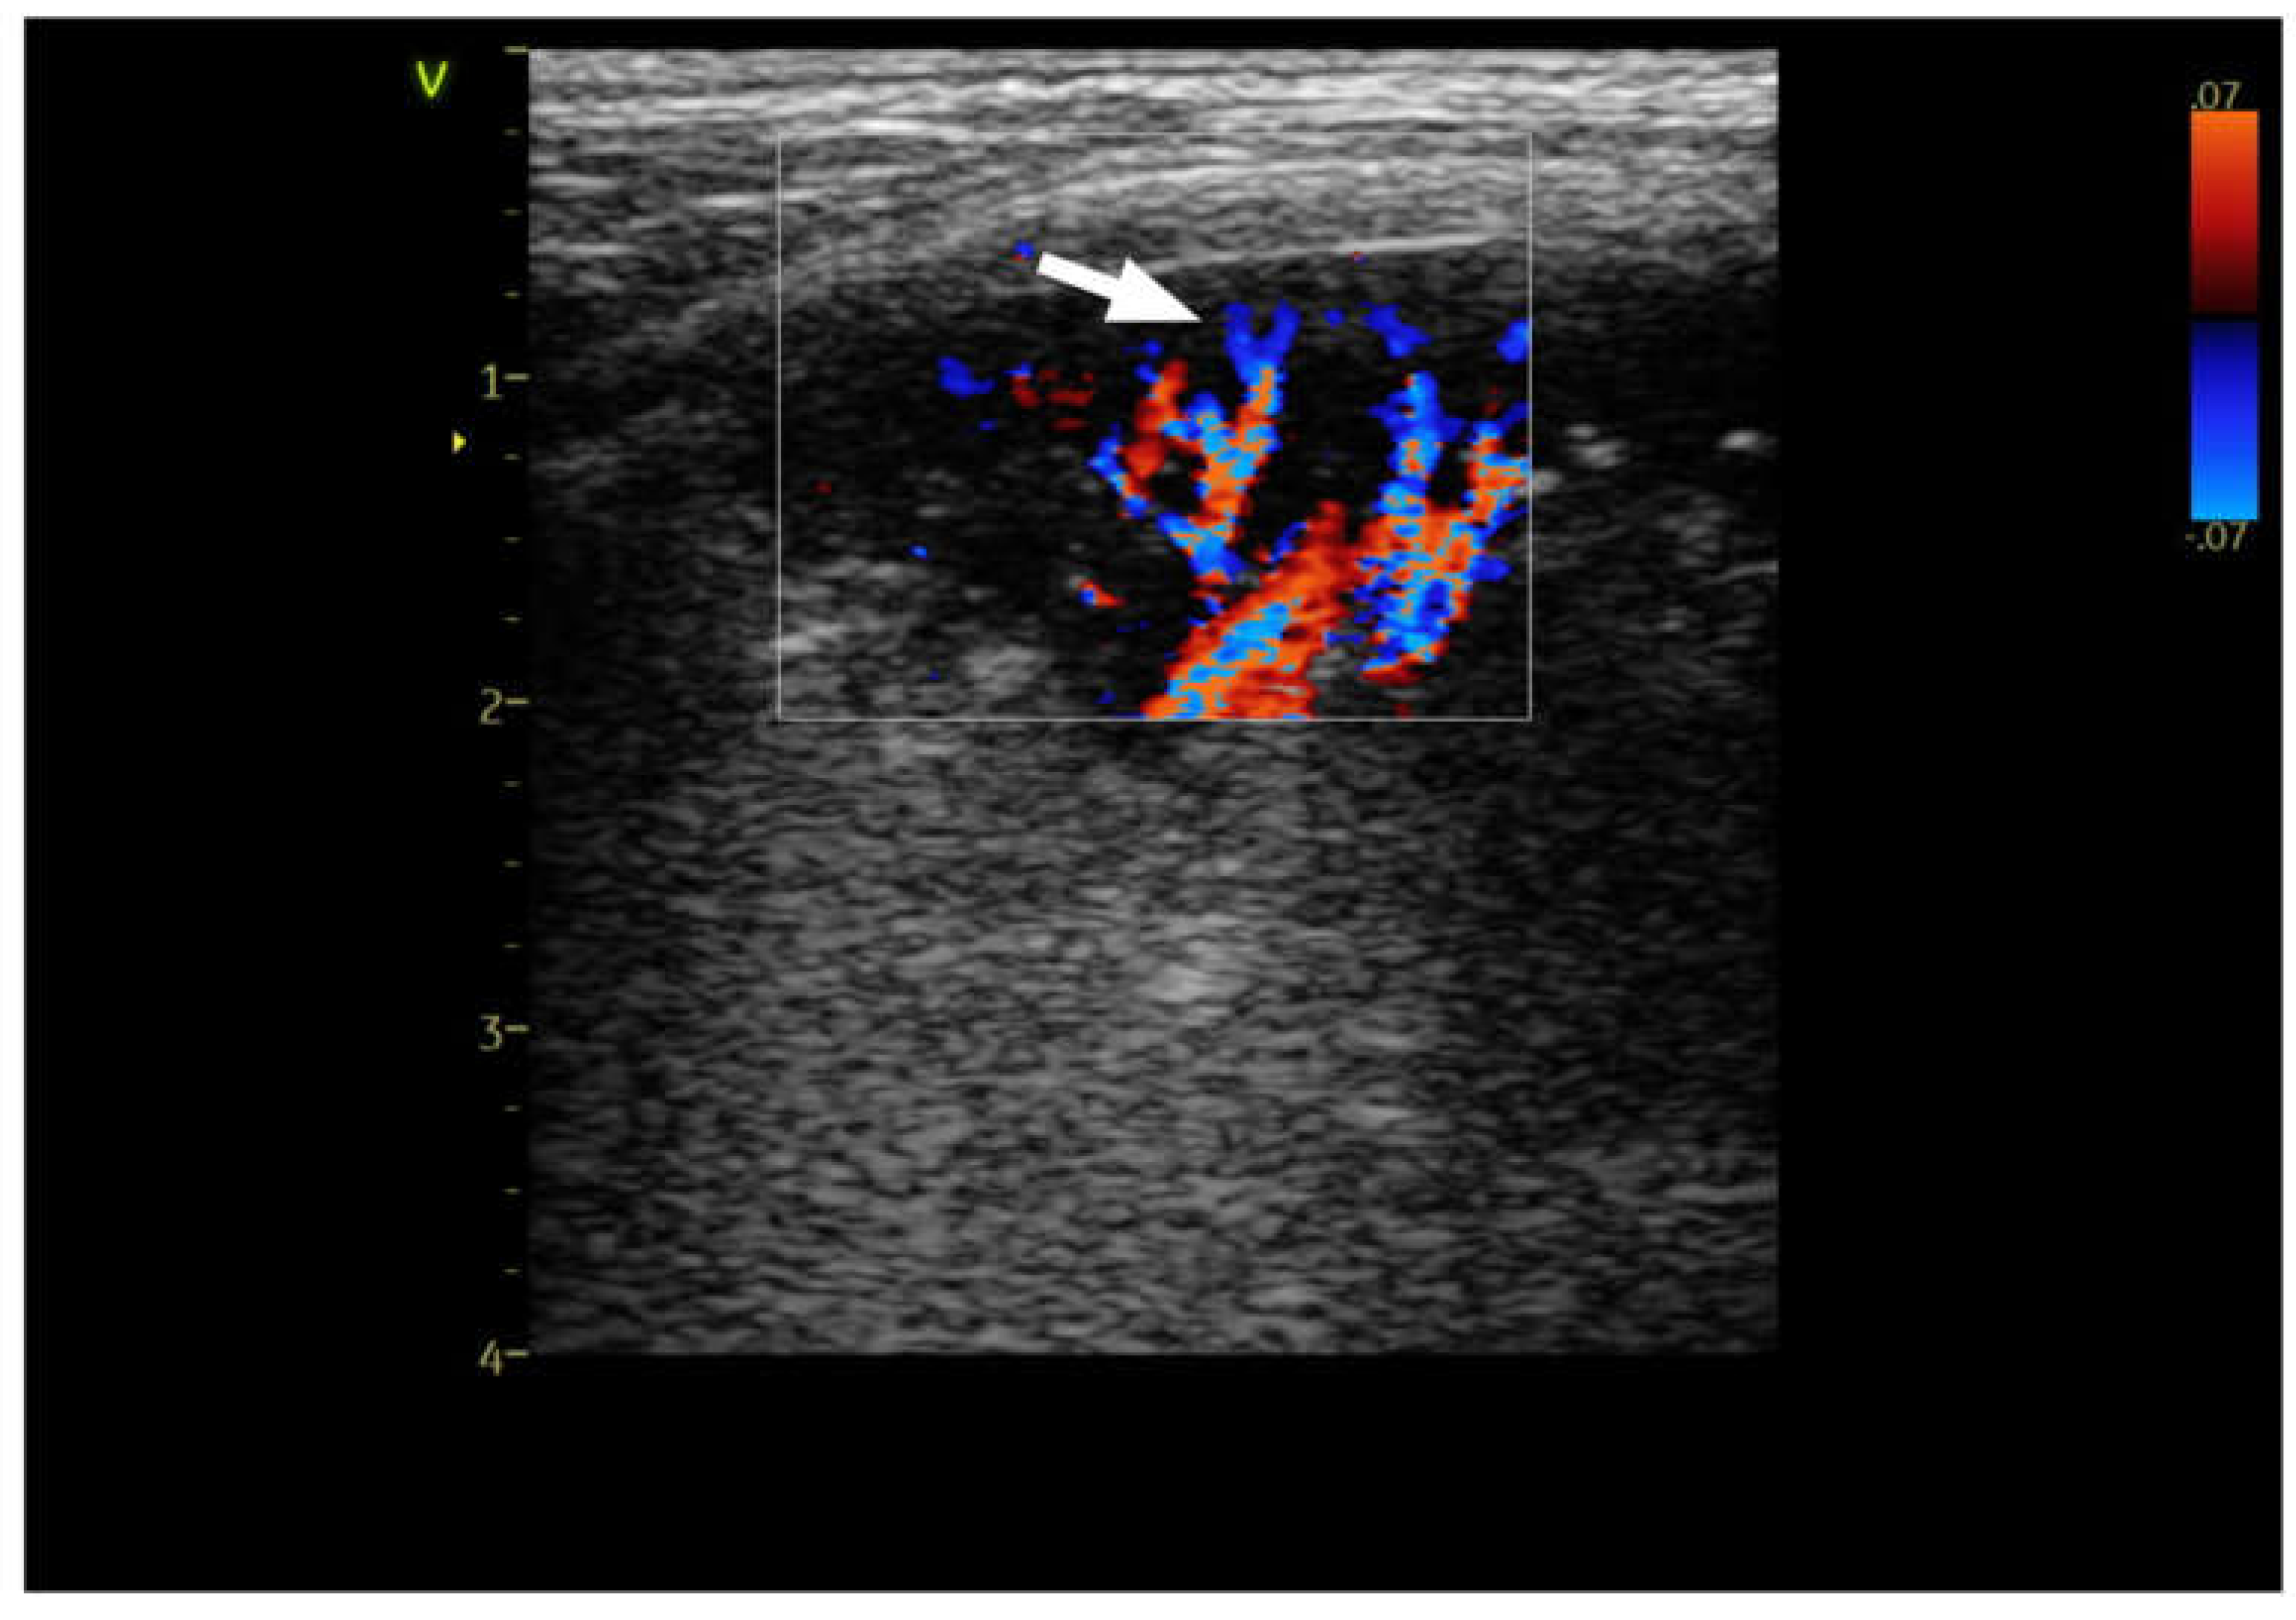

| CD | color doppler | |

| Hv | chaotic type vascularity | |

| Pv | penetrating type vascularity | |

| Rv | residual type vascularity | |

| Tv | tree-like vascularity | |